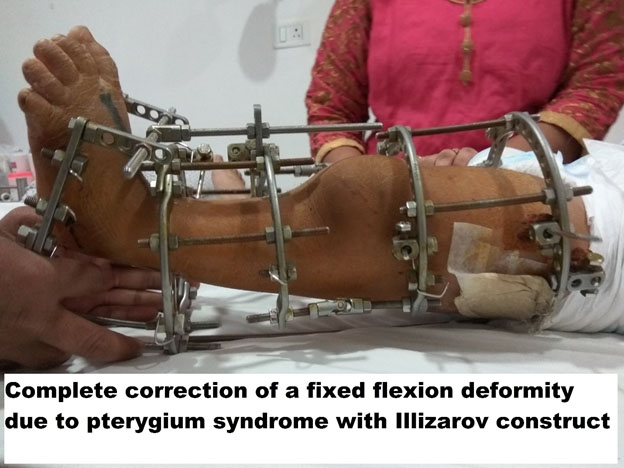

GENU PROCURVATUM & FIXED FLEXION DEFORMITY OF KNEE (FFD)

FFD is a deformity where there is anterior convex bowing of the knee joint. This could be caused for various reasons which include-

Trauma

Cerebral Palsy

Infection

Prolonged immobilization

Congenital abnormality

The clinical findings in this situation are inability or difficulty for the patient to walk. There will be a gross limb length difference leading to severe functional impairment. Many times, these patients are confined to wheelchair, and that leads to further contractures.

Treatment of this condition depends on the underlying cause and status of the knee joint. Growth modulation surgery is offered if there is a growth plate abnormality. If there is arthritis of the knee joint, then arthritis treatment might have to be combined with deformity correction.

CASE 1

Post-traumatic with surgical fixation leading to a 60-degree flexion deformity in a 30-year-old female patient who was walking with difficulty. After six weeks of distraction, please note the achievement of full extension.

Case 2

A 10-year-old boy who presented with Fixed flexion deformity of the knee, had repeated failed surgeries (2 number) as part of a complex pterygium syndrome and difficulty in gait.